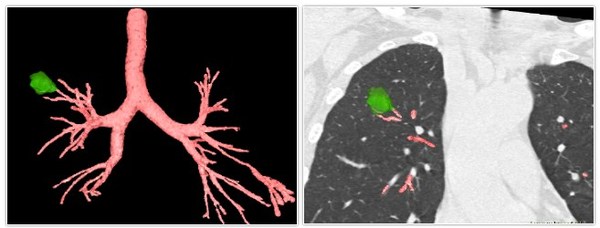

本例手术由李时悦教授和钟长镐医生共同完成。患者62岁,一年前因右下肺腺癌进行外科手术,接受一年术后化疗,2020年8月右肺上叶复发,不适合再进行外科手术,肺部肿瘤消融手术为目前最佳治疗方式。患者结节为大小约24*16mm的磨玻璃结节,位于右上叶前段。术前,使用LungPro增强现实全肺诊疗导航系统进行路径规划。

术中,在LungPro的实时同步引导下,术者根据导航路径信息,送入射频消融导管,消融时间300秒,顺利完成肿瘤消融治疗。术后,病人无气胸、喘息、出血等并发症出现。